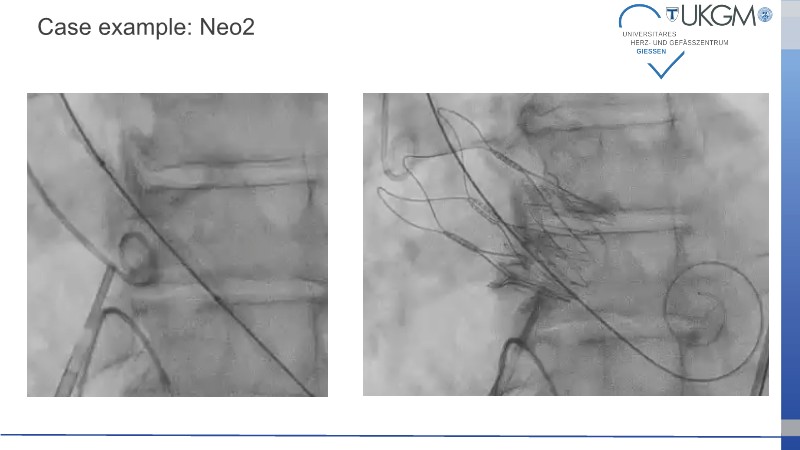

This session addresses recent advancements and ongoing challenges in transcatheter aortic valve implantation (TAVI), with a particular focus on valve selection during index procedures. Presentations include data from the Accurate IDE trial, highlighting the prognostic implications of valve underexpansion. A clinical case involving an 80-year-old patient with severe aortic stenosis and multiple comorbidities illustrates the importance of personalized procedural planning, particularly in terms of vascular access and valve positioning. The session also emphasizes the value of lifetime patient management strategies, including coronary access and the feasibility of redo TAVI, supported by simulation.